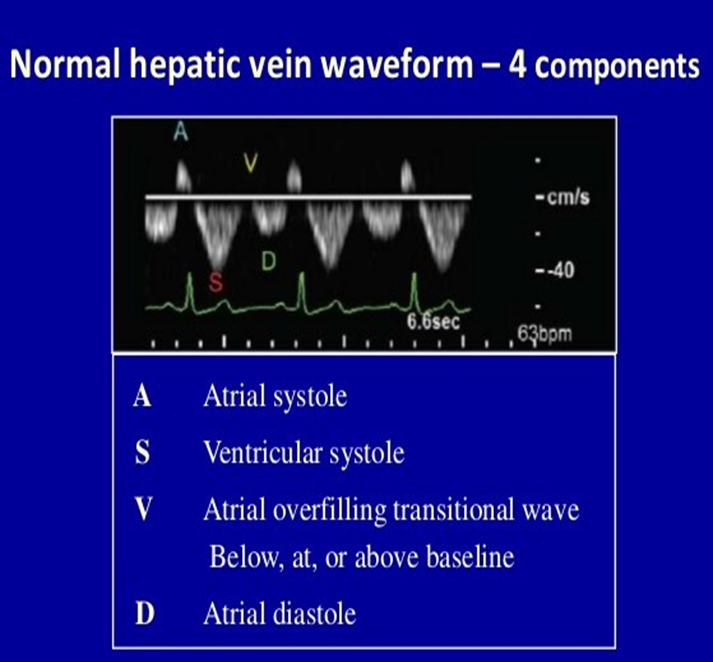

Normal hepatic vein flow travels _____ from the transducer towards the IVC and is encoded in _____

away/ blue.

TR flowing into the IVC & Hepatic veins will flow ______ the transducer during systole and is encoded in _____

towards/red

On the spectral waveform, this systolic flow will appear _____ the baseline (______)

(color & spectral flow reversal of the hepatic veins)

above/ antegrade

The hepatic vein waveform can be reflective of the ______

severity of TR present.

The more severe the regurgitation, the more _______ the hepatic waveform becomes.

pulsatile

anything above baseline means flow reversal

How to prove severe TR